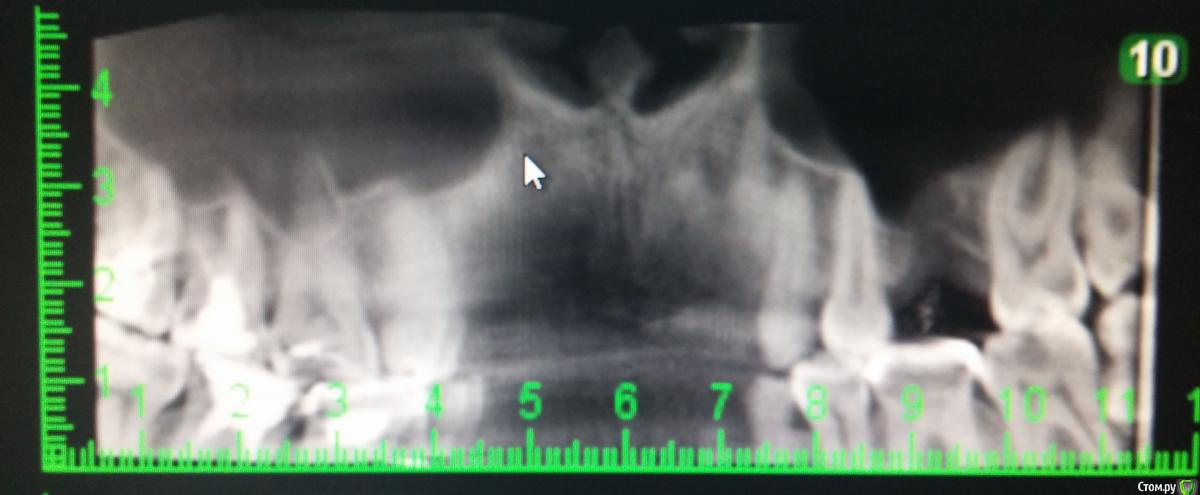

Yudjin Опубликовано 11 июня, 2015 Поделиться Опубликовано 11 июня, 2015 Добрый день! Уважаемые врачи, требуется Ваша консультация. Ситуация следующая: ЛОР обнаружил кисту в гайморовой пазухе, направил к стоматологу, тот, после осмотра снимка, решительно настоял на удалении верхней 6-ки, т.к. корень заходил в гайморову пазуху и способствовал образованию кисты...Зуб удалили, и через образовавшуюся "дырку" удалили кисту. Стоматолог посоветовал поставить имплант, но т.к. кости вообще не было, подсадили костную ткань. Прошло 6 мес. сделал 3D снимок, который показал наличие кости в 5 мм. Врач сказал, что на такую кость имплант ставить нельзя, нужно будет подсаживать костную ткань еще раз и ставить мембрану. Окончательная цена вырастает в разы...Теперь к моему вопросу: стоит ли продолжать манипуляции по установке импланта или установить коронку на соседний здоровый зуб и поставить мост? и если ставить мост, можно ли оставлять костную ткань в таком состоянии и чем чревато? Ссылка на комментарий

Alejandro Опубликовано 12 июня, 2015 Поделиться Опубликовано 12 июня, 2015 К сожалению, в нашей стране имплантация не является основным методом замещения дефекта зубного ряда, а всего лишь метод выбора. Поэтому постановку мостовидного протеза здесь произвести возможно. Только учитывайте все негативные последствия данной процедуры, в том числе атрофию костной ткани под промывной частью мостовидного протеза (место отсутствующего зуба). Да, и кстати, обрабатывать под коронки здесь прийдётся минимум 3 зуба, чтобы сильно не перегружать. Относительно синуслифтинга. Кроме цены Вас не должно ничего смущать: в умелых руках доктора это рядовая процедура, к которой он всегда готов, даже внепланово.PS А почему высоту альвеоляра померили с середины? 1 Ссылка на комментарий

Yudjin Опубликовано 14 июня, 2015 Автор Поделиться Опубликовано 14 июня, 2015 К сожалению, в нашей стране имплантация не является основным методом замещения дефекта зубного ряда, а всего лишь метод выбора. Поэтому постановку мостовидного протеза здесь произвести возможно. Только учитывайте все негативные последствия данной процедуры, в том числе атрофию костной ткани под промывной частью мостовидного протеза (место отсутствующего зуба). Да, и кстати, обрабатывать под коронки здесь прийдётся минимум 3 зуба, чтобы сильно не перегружать. Относительно синуслифтинга. Кроме цены Вас не должно ничего смущать: в умелых руках доктора это рядовая процедура, к которой он всегда готов, даже внепланово.PS А почему высоту альвеоляра померили с середины?примерно так мерил высоту стоматолог, у него даже еще меньше получилось, примерно 4.55 мм. А какие будут все негативные последствия после установки моста? и что такое атрофия костной ткани? Ссылка на комментарий